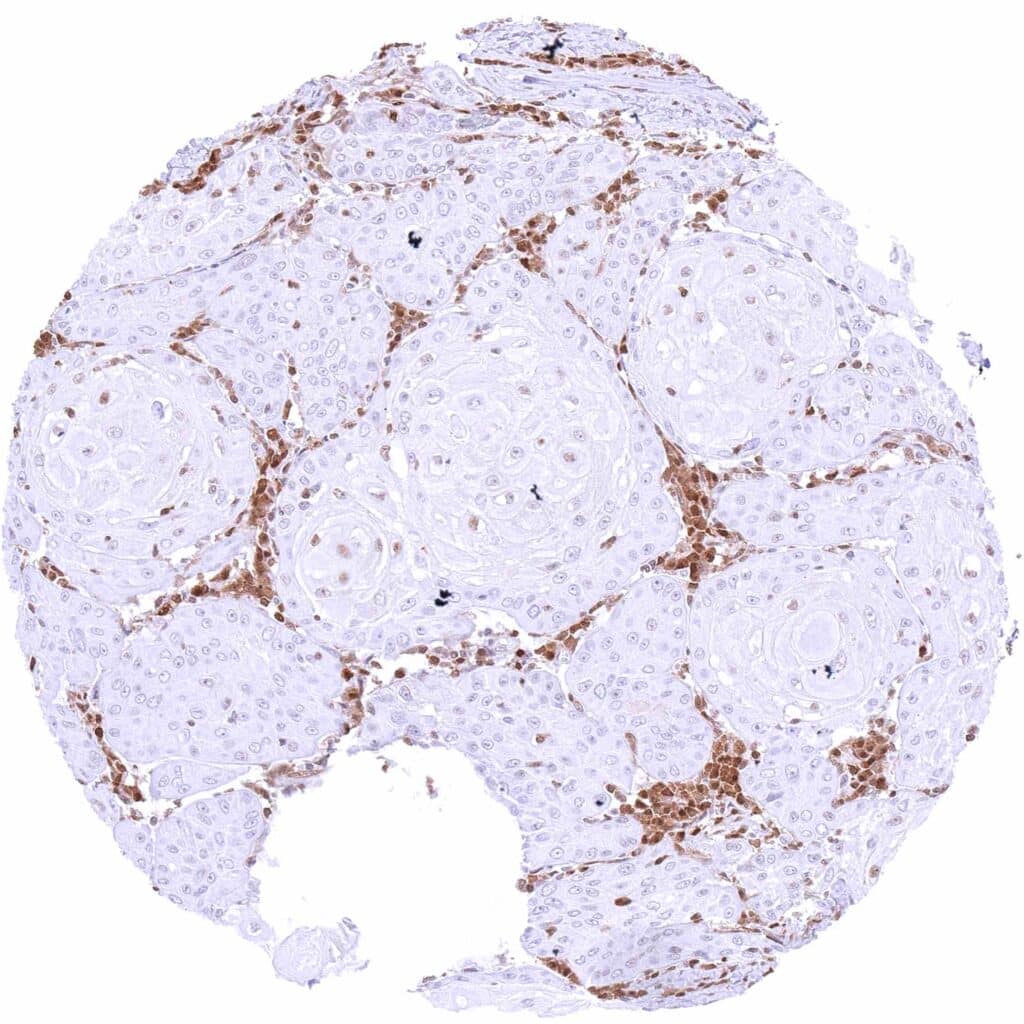

Testis – p27 negative seminoma with strong p27 staining of inflammatory cells and other stroma cells.